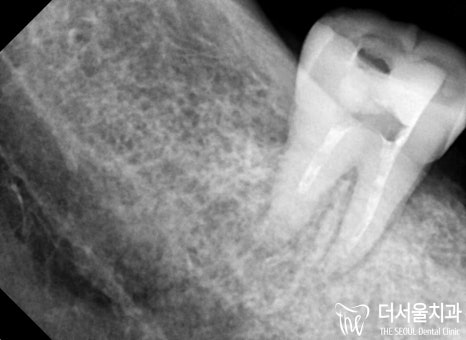

더 서울에서 정확한 진단을 위해

엑스레이 촬영을 진행한 결과,

하악 우측 잔존 어금니는 심한 충치로 인해

병소가 치수까지 감염되어 있었습니다.